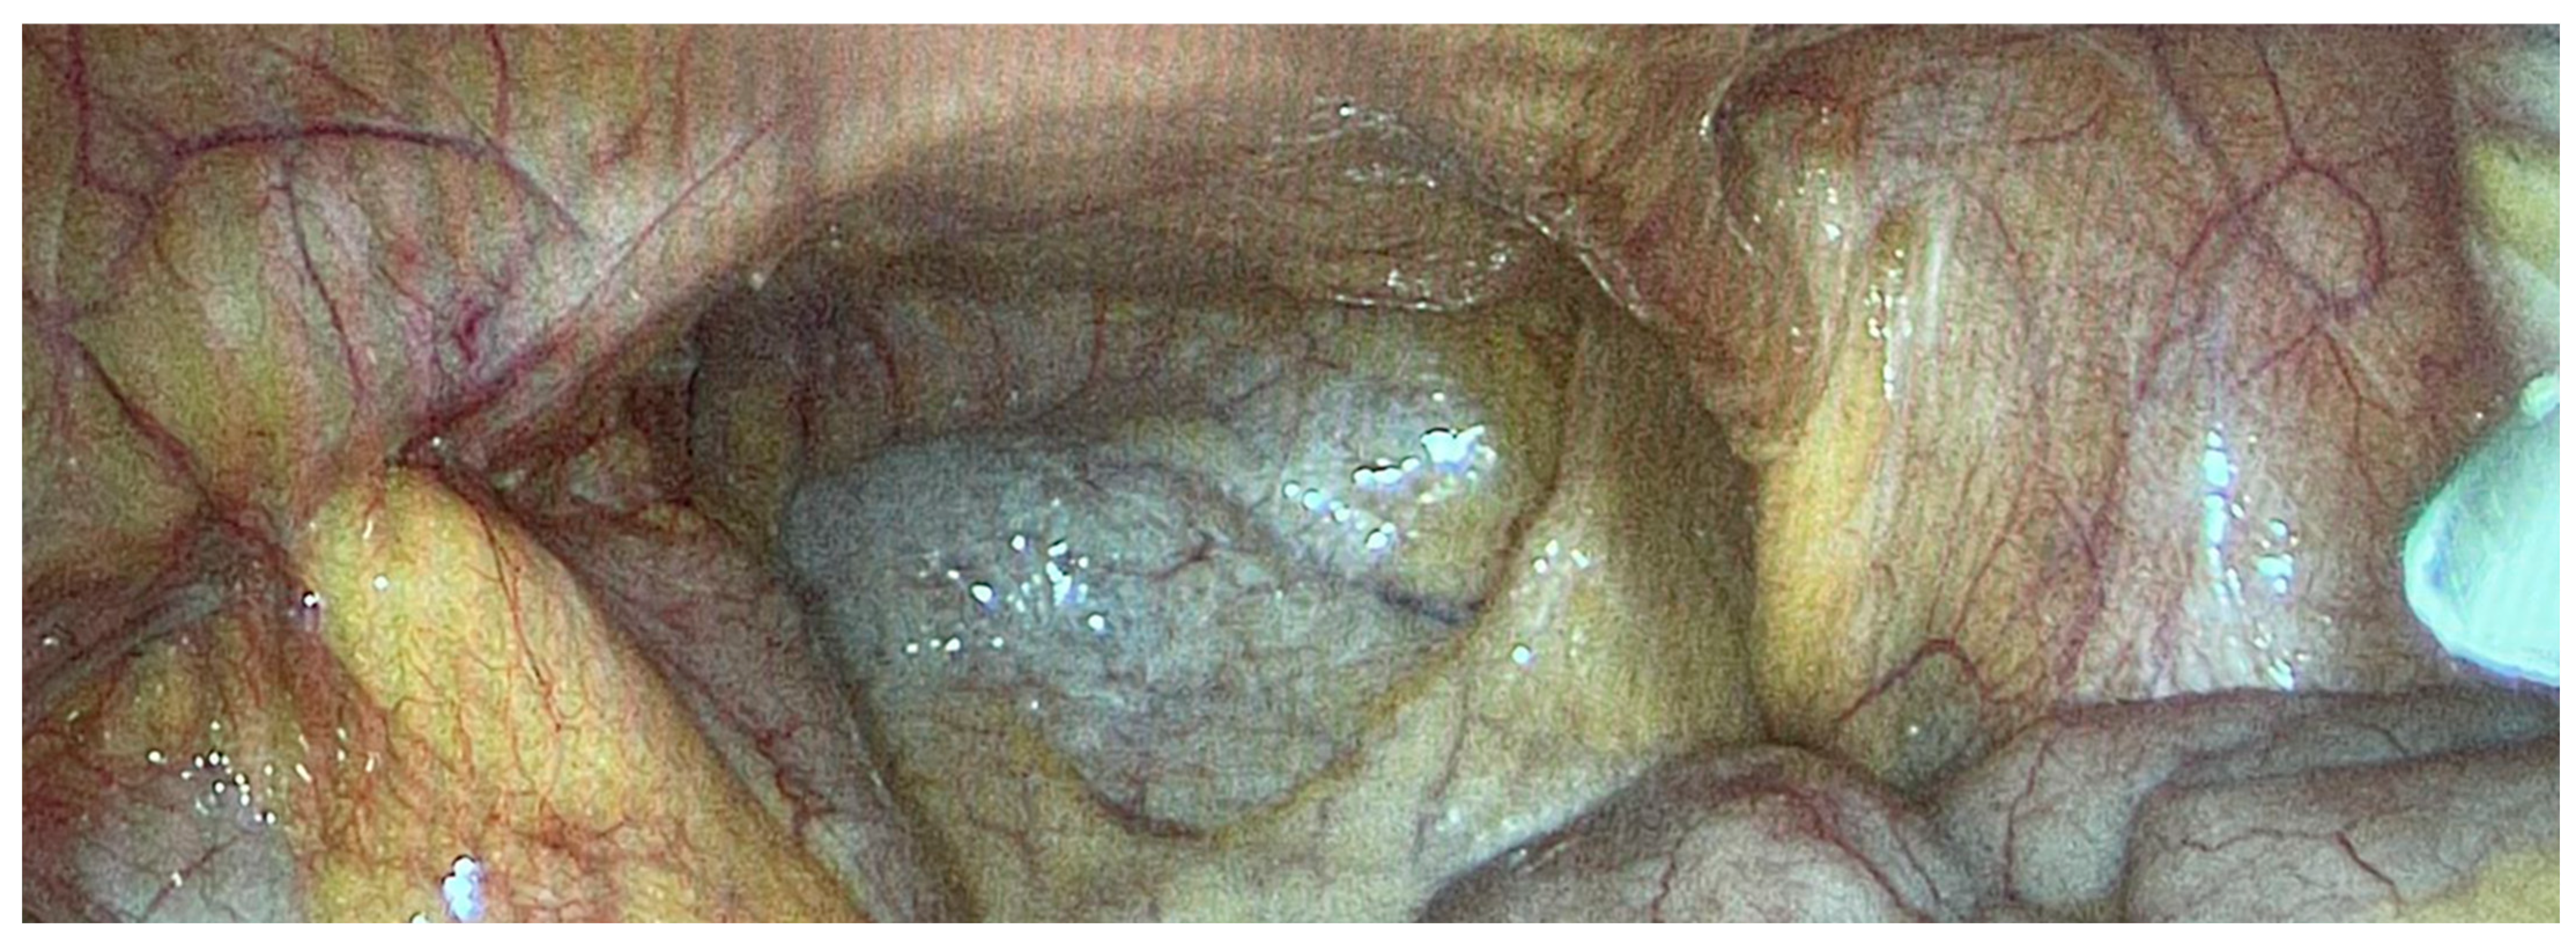

We operated on six female patients with primary high-grade peritoneal cancer. The mean age was 66 years (42–77 years). All had primary surgery in different gynaecological departments, and all were referred to our department due to intra-abdominal tumour recurrence. We used carboxyplatin AUC 1.5–3 in these cases. The number of PIPAC procedures varied from three to six. One patient refused further treatment using this technique after the third PIPAC, despite a reduction in sPCI after the first PIPAC. We stopped PIPAC treatment in three cases due to disease progression in the abdominal cavity and liver metastases. One patient was indicated for surgery and HIPEC after the sixth procedure. There was a decrease in sPCI: the initial value was 10 and decreased to 6 during the last PIPAC according to sPCI. Surprisingly, the PRGS score was unchanged at 4, which indicated no effect. However the decrease in carcinomatosis extent was clear (Figure 4 and Figure 5). Unfortunately, there was also tumour progression in the omental bursa according to preoperative PET-CT. We found that the tumour surrounded the celiac trunk and its branches (except for involvement of both diaphragms); therefore, radical surgery was impossible. Interestingly, there was sPCI regression in this group of patients, but the PRGS score was usually unchanged. The last patient, a 77-year-old woman with diaphragm, small pelvis and small bowel involvement according to preoperative PET-CT, was indicated for PIPAC due to her age and an expectedly high sPCI. Surprisingly, we found only minimal disease (sPCI 1), and she was indicated for CRS + HIPEC.

Figure 4.

Primary peritoneal cancer PIPAC 1.

Figure 5.

Primary peritoneal cancer PIPAC 6.